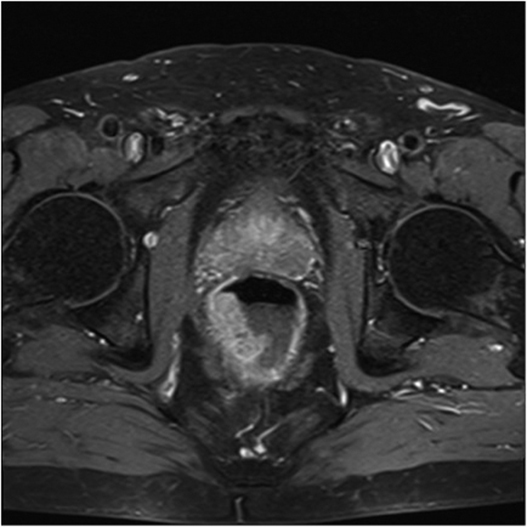

Fig1. Pacient cu neoplasm rectal stadiul IIIC (T3; N2; M0) confirmat bioptic, adenocarcinom mixt G2

a-d imagini T2 ponderate în plan sagital, oblic axial și oblic coronal – masă tisulară dezvoltată superior de joncțiunea anorectală, lateral dreapta, cu minimă extensie la nivelul grăsimii mezorectale și limfoganglioni mezorectali cu diametru de până la 10 mm;